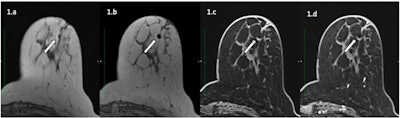

Overall, the Swiss authors report that magnetic markers are widely visible on MRI images due to the susceptibility artifact that they generate.

"However, the same artifact that accounts for visibility of the marker can possibly mask or mimic, depending on the circumstances, a residual tumoral enhancement and thus reduce the diagnostic accuracy of MRI," they wrote. "Indeed, the size and appearance of metallic artifact on MRI depends on several factors, namely the material of the clip (in particular its magnetic susceptibility), the magnetic field strength of the system, and the sequence itself (gradient echo or spin echo are not equally sensitive to the presence of metal)."